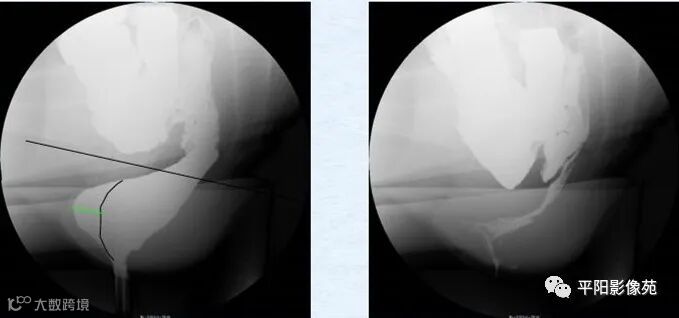

会阴下降(perineum descending,PD)是指用力排便时肛上距≥31mm(经产妇≥36mm)者。伴有其他异常时称之为会阴下降综合征(descending perineum syndrome,DPS)。(图1)

图1 力排时肛上距明显增大>31mm

直肠前壁黏膜脱垂(anterior mucosal prolapse,AMP)是指增粗而松弛的直肠黏膜脱垂于肛管上部前方。造影时见该部呈凹陷状,而直肠肛管结合部的后缘则光滑连续。(图2)

图2 直肠前壁局部凹陷,提示黏膜脱垂